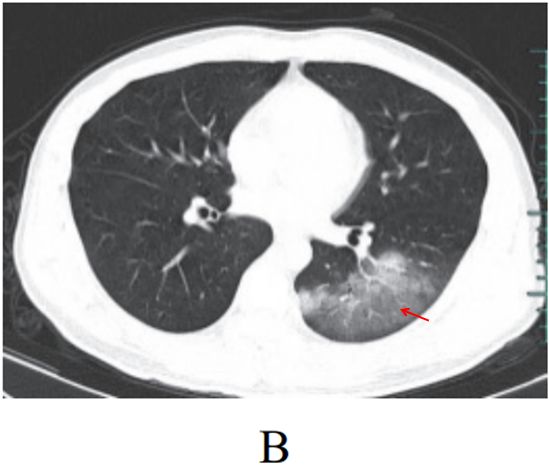

与肺部支原体感染的鉴别诊断

支原体肺炎是由支原体引起的以间质性改变为主的肺炎。支原体侵入肺内可引起支气管、细支气管黏膜及周围间质充血和水肿,多核细胞浸润,侵入肺泡可产生肺泡浆液性渗出炎症。病变范围可从小叶、肺段至大叶。多数患者症征不符:临床症状重,影像学表现较轻。

实验室检查支原体抗体呈阳性,发病 2~3 周后血冷凝集试验比值升高(可达 1∶64)。

影像学表现:

(1) HRCT 显示更清晰,呈树雾征(图 3-13A)、树芽征(图 3-13B),可出现支气管壁增厚。

(2)渗出实变较淡,常合并支气管肺炎。